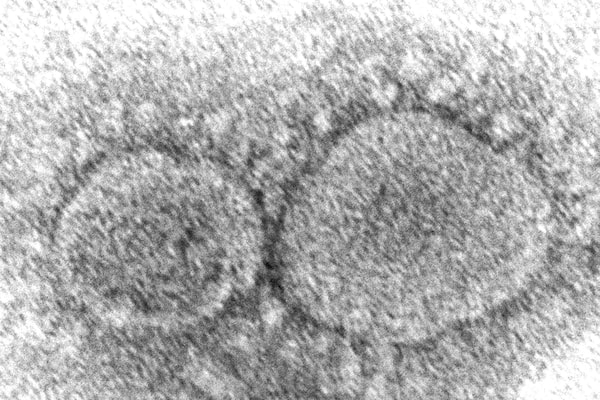

This 2020 electron microscope image made available by the Centers for Disease Control and Prevention shows SARS-CoV-2 virus particles which cause COVID-19.Hannah A. Bullock/The Associated Press